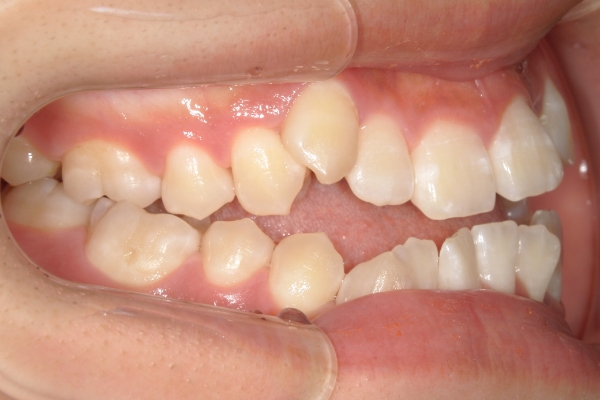

PROCESS

3か月

骨格的に下あごが前下方に長いことが原因で、受け口、開咬(前歯が当たらない)の症状がでていました。また下あごが右にずれており、その影響で上下の歯列正中(真ん中)の大きなずれも生じていました。顎変形症手術も選択肢の一つでしたが、患者さまの希望もあり、下顎左側小臼歯の抜歯をして通常の歯列矯正で治療をしました。

前歯、奥歯の噛み合わせが大きく改善され、上下の歯真ん中が一致しました。食べ物が噛みやすくなったこともですが、歯列の見た目が整った点にも患者さまは満足されていました。